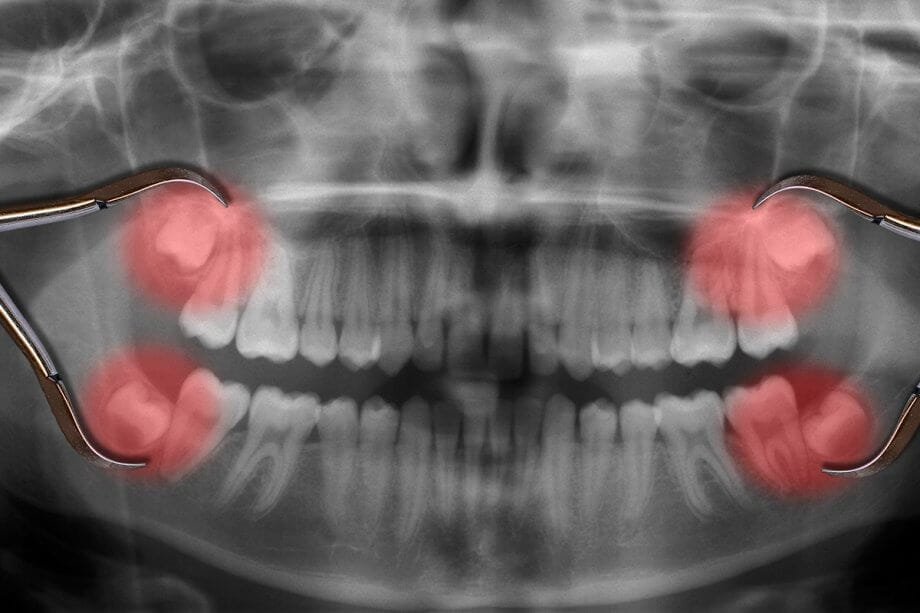

Dental implants are a fantastic solution for replacing missing teeth, offering durability, comfort, and a natural appearance. However, like any dental treatment, they can sometimes encounter issues. One common concern is a loose dental implant. But don’t worry! In most cases, a loose dental implant can be fixed with the right approach. Let’s dive into […]